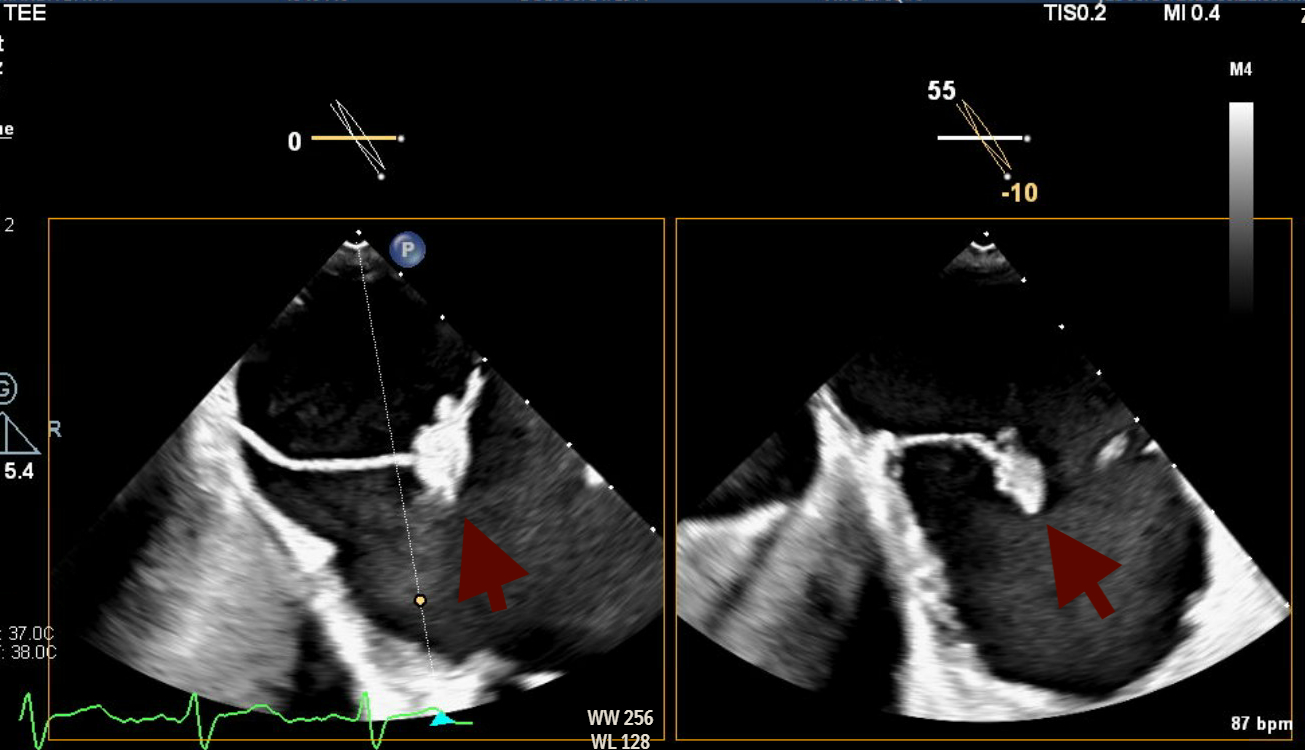

Abstract Body (Do not enter title and authors here): Here is a rare and diagnostically challenging case of infective endocarditis (IE) involving the Chiari network in a 47-year-old female with a complex cardiac and social history. She had a history of intravenous drug use (IVDU), prior methicillin-sensitive Staphylococcus aureus (MSSA) bacteremia involving the mitral valve (MV), and methicillin-resistant Staphylococcus aureus (MRSA) endocarditis requiring tricuspid valve (TV) replacement with a CorMatrix bioprosthesis. She presented with a 3-day history of fever, progressive right groin pain and swelling, and worsening dyspnea. On admission, she was afebrile but hypotensive and had tachycardia. On examination, she had a loud holosystolic murmur in the left lower sternal border, a pulsatile right groin mass with a bruit, alongside multiple healed track marks on her lower extremities. Blood work was notable for leukocytosis. Computed tomography of the chest, abdomen, and pelvis revealed multiple pulmonary septic emboli and a right femoral artery pseudoaneurysm with an arteriovenous fistula confirmed on duplex ultrasound. Transthoracic echocardiogram (TTE) showed preserved ejection fraction (60-65%), normal aortic and mitral valves, but poor visualization of the prosthetic tricuspid valve. Blood cultures grew MRSA, and the patient was started on IV vancomycin. Transesophageal echocardiogram (TEE) revealed a large, mobile echogenic mass attached to the Chiari network (CN), positioned in line with the tricuspid regurgitant jet. These new findings, absent on prior imaging, strongly suggested isolated Chiari network endocarditis (CNE)

Right-sided infective endocarditis (IE) is a rare clinical entity, accounting for less than 10% of all IE cases. Among these, involvement of the CN- the embryonic remnant of the right valve of the sinus venosus and present in under 2% of the population- is even rarer, with only a few reported cases to date. IVDU remains the leading risk factor for right-sided IE, as seen in our patient. The true incidence of CNE is likely underreported due to the limited sensitivity of TTE, which can make visualizing it challenging. TEE remains the imaging modality of choice for identifying such atypical presentations.

Our case reinforced the critical role of TEE in identifying uncommon, non-valvular sources of infection. In the absence of clear treatment guidelines and high surgical risk, the patient was treated conservatively with a 6-week course of antibiotics followed by repeat TEE for monitoring.